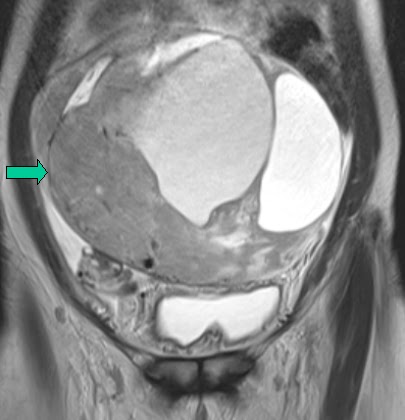

| Coronal T2 |

Diffuse hyperintense signal uniform heterogenous thickening of the endometrium on the T2 images that is intermediate signal on T1.

The hyperplasia extends to into the cervical canal bulging through the external os.

This is was histologically proven to be Endometrial hyperplasia.